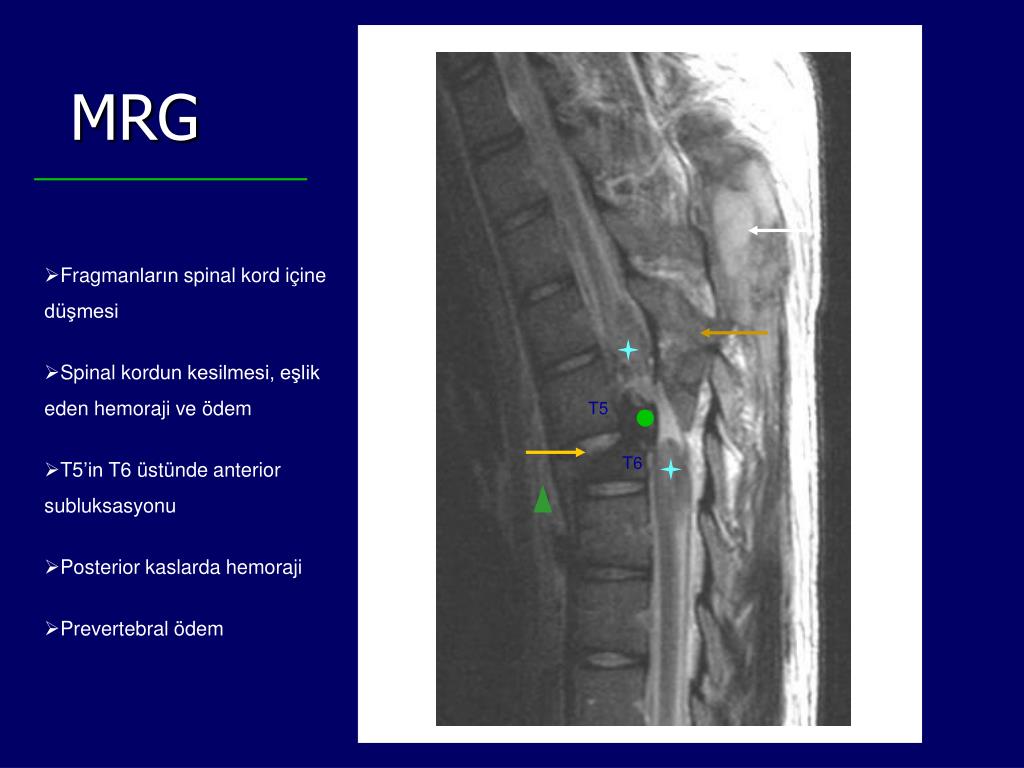

13. MRG Sagittal T2 • Fragmanların spinal kord içine düşmesi • Spinal kordun kesilmesi, eşlik eden hemoraji ve ödem • T5’in T6 üstünde anterior subluksasyonu • Posterior kaslarda hemoraji • Prevertebral ödem T5 T6